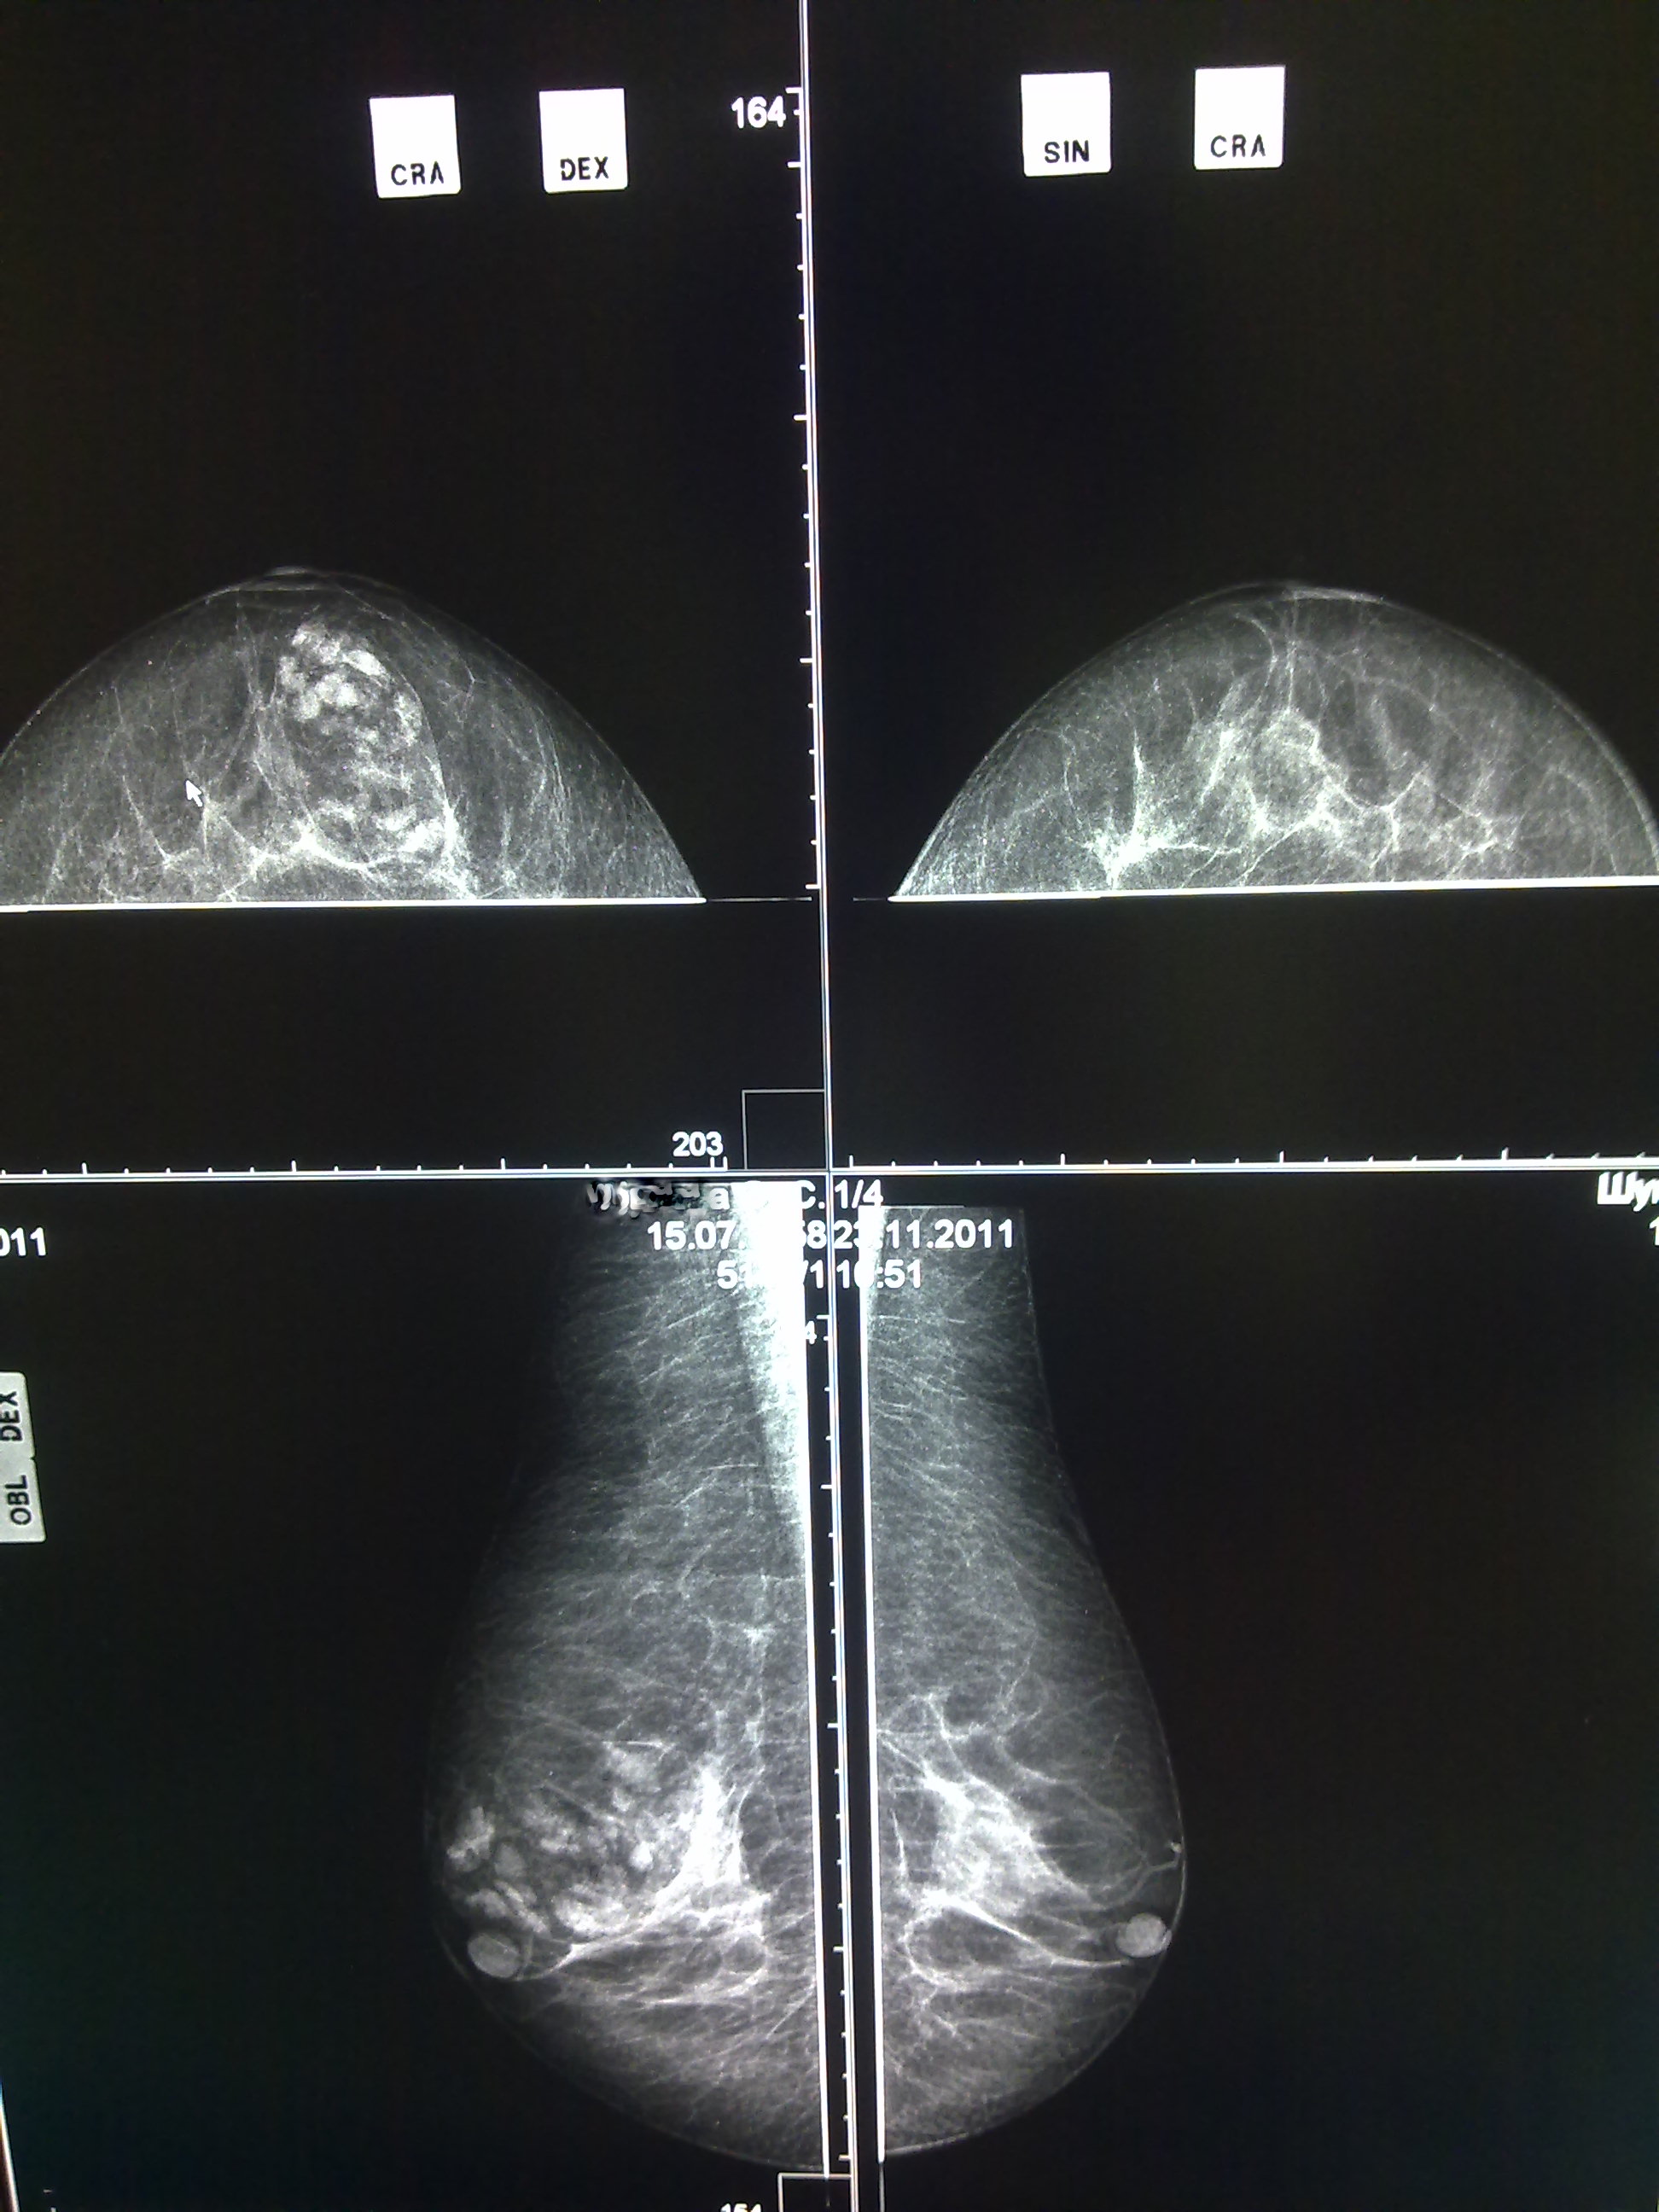

Женщина, 1958 г.р, пришла на маммоскрининг, до этого не обследовалась,ничего не беспокоит. Помогите, пожалуйста определиться, что это, множественные фиброаденомы? рак?

думаю надо делать цитологию. всякое может быть. просто опишите .

Скорее всего кисты на фоне расширеных протоков. О чем-то подробнее, при таком качестве картинки, говорить нельзя.